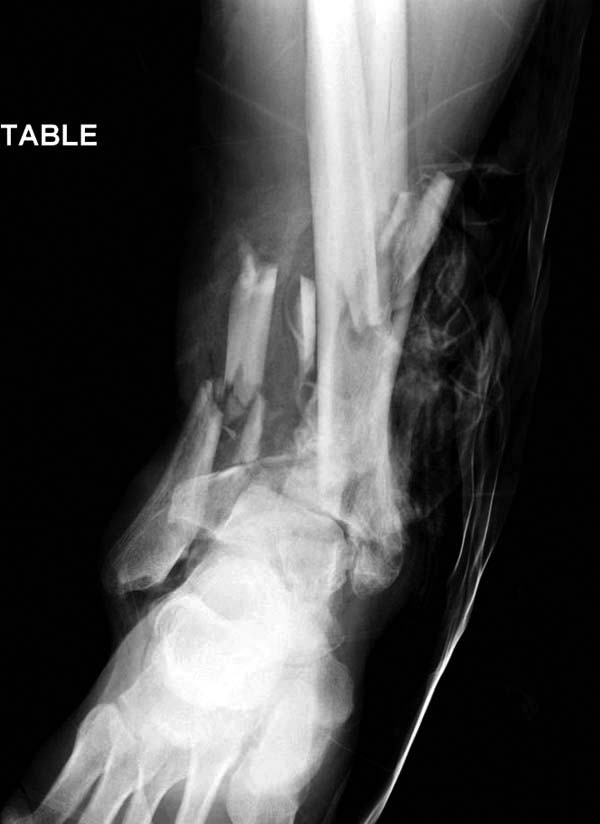

В нашем случае, травма в результате коллапса крыши. Открытый перелом. Ургентные Irrigation and Debridment, дистракция наружным фиксатором. В госпиталях первого уровня редко бывает изолированная травма, и на другой стороне повреждение стопы с переломом навикулярной кости. После обработки раны - вакуум и двухсторонние наружные фиксаторы.

Вначале нет смысла заказывает КТ, только дистракция организует на свое место свободных фрагментов. По топографии отломком преоперационный план, а готовность мягкой ткани подтвердит появившиеся морщины на поверхности кожи, “Wrinkle Sign”.